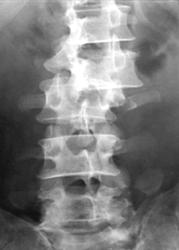

Признаком взрывных переломов, выявляемых при обзорной рентгенографии, является увеличение интерпедикулярного расстояния на прямой рентгенограмме (рис. 2А), увеличение переднезаднего размера тела позвонка - на боковой (рис. 2Б) и локальная кифотическая деформация в зоне перелома.

|

| А |

Б |

| Рис. 2. Рентгенологические признаки взрывного перелома тела позвонка |